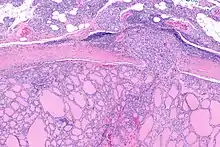

Micrograph of follicular thyroid carcinoma showing a location where the cancer grows through the fibrous capsule. H&E stain.